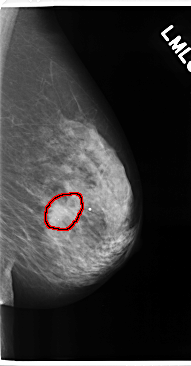

C_0175_1.LEFT_CC

LEFT_CC LINES 4728 PIXELS_PER_LINE 2752 BITS_PER_PIXEL 12 RESOLUTION 50 OVERLAY

FILE: C_0175_1.LEFT_CC.OVERLAY

TOTAL_ABNORMALITIES 1

ABNORMALITY 1

LESION_TYPE MASS SHAPE IRREGULAR MARGINS ILL_DEFINED

ASSESSMENT 5

SUBTLETY 4

PATHOLOGY MALIGNANT

TOTAL_OUTLINES 1

BOUNDARY